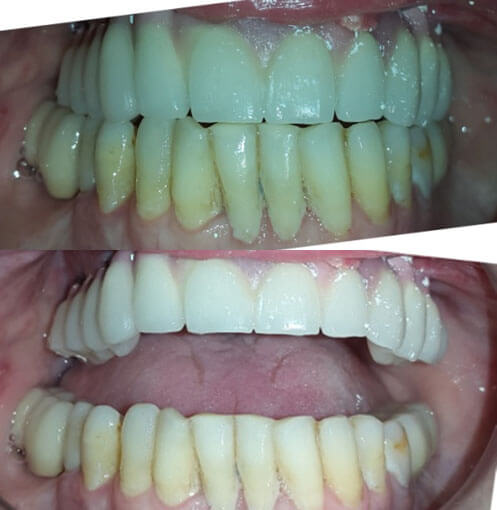

Имплантации зубов и реконструкции челюсти – Зубные имплантаты экзоскелетного типа